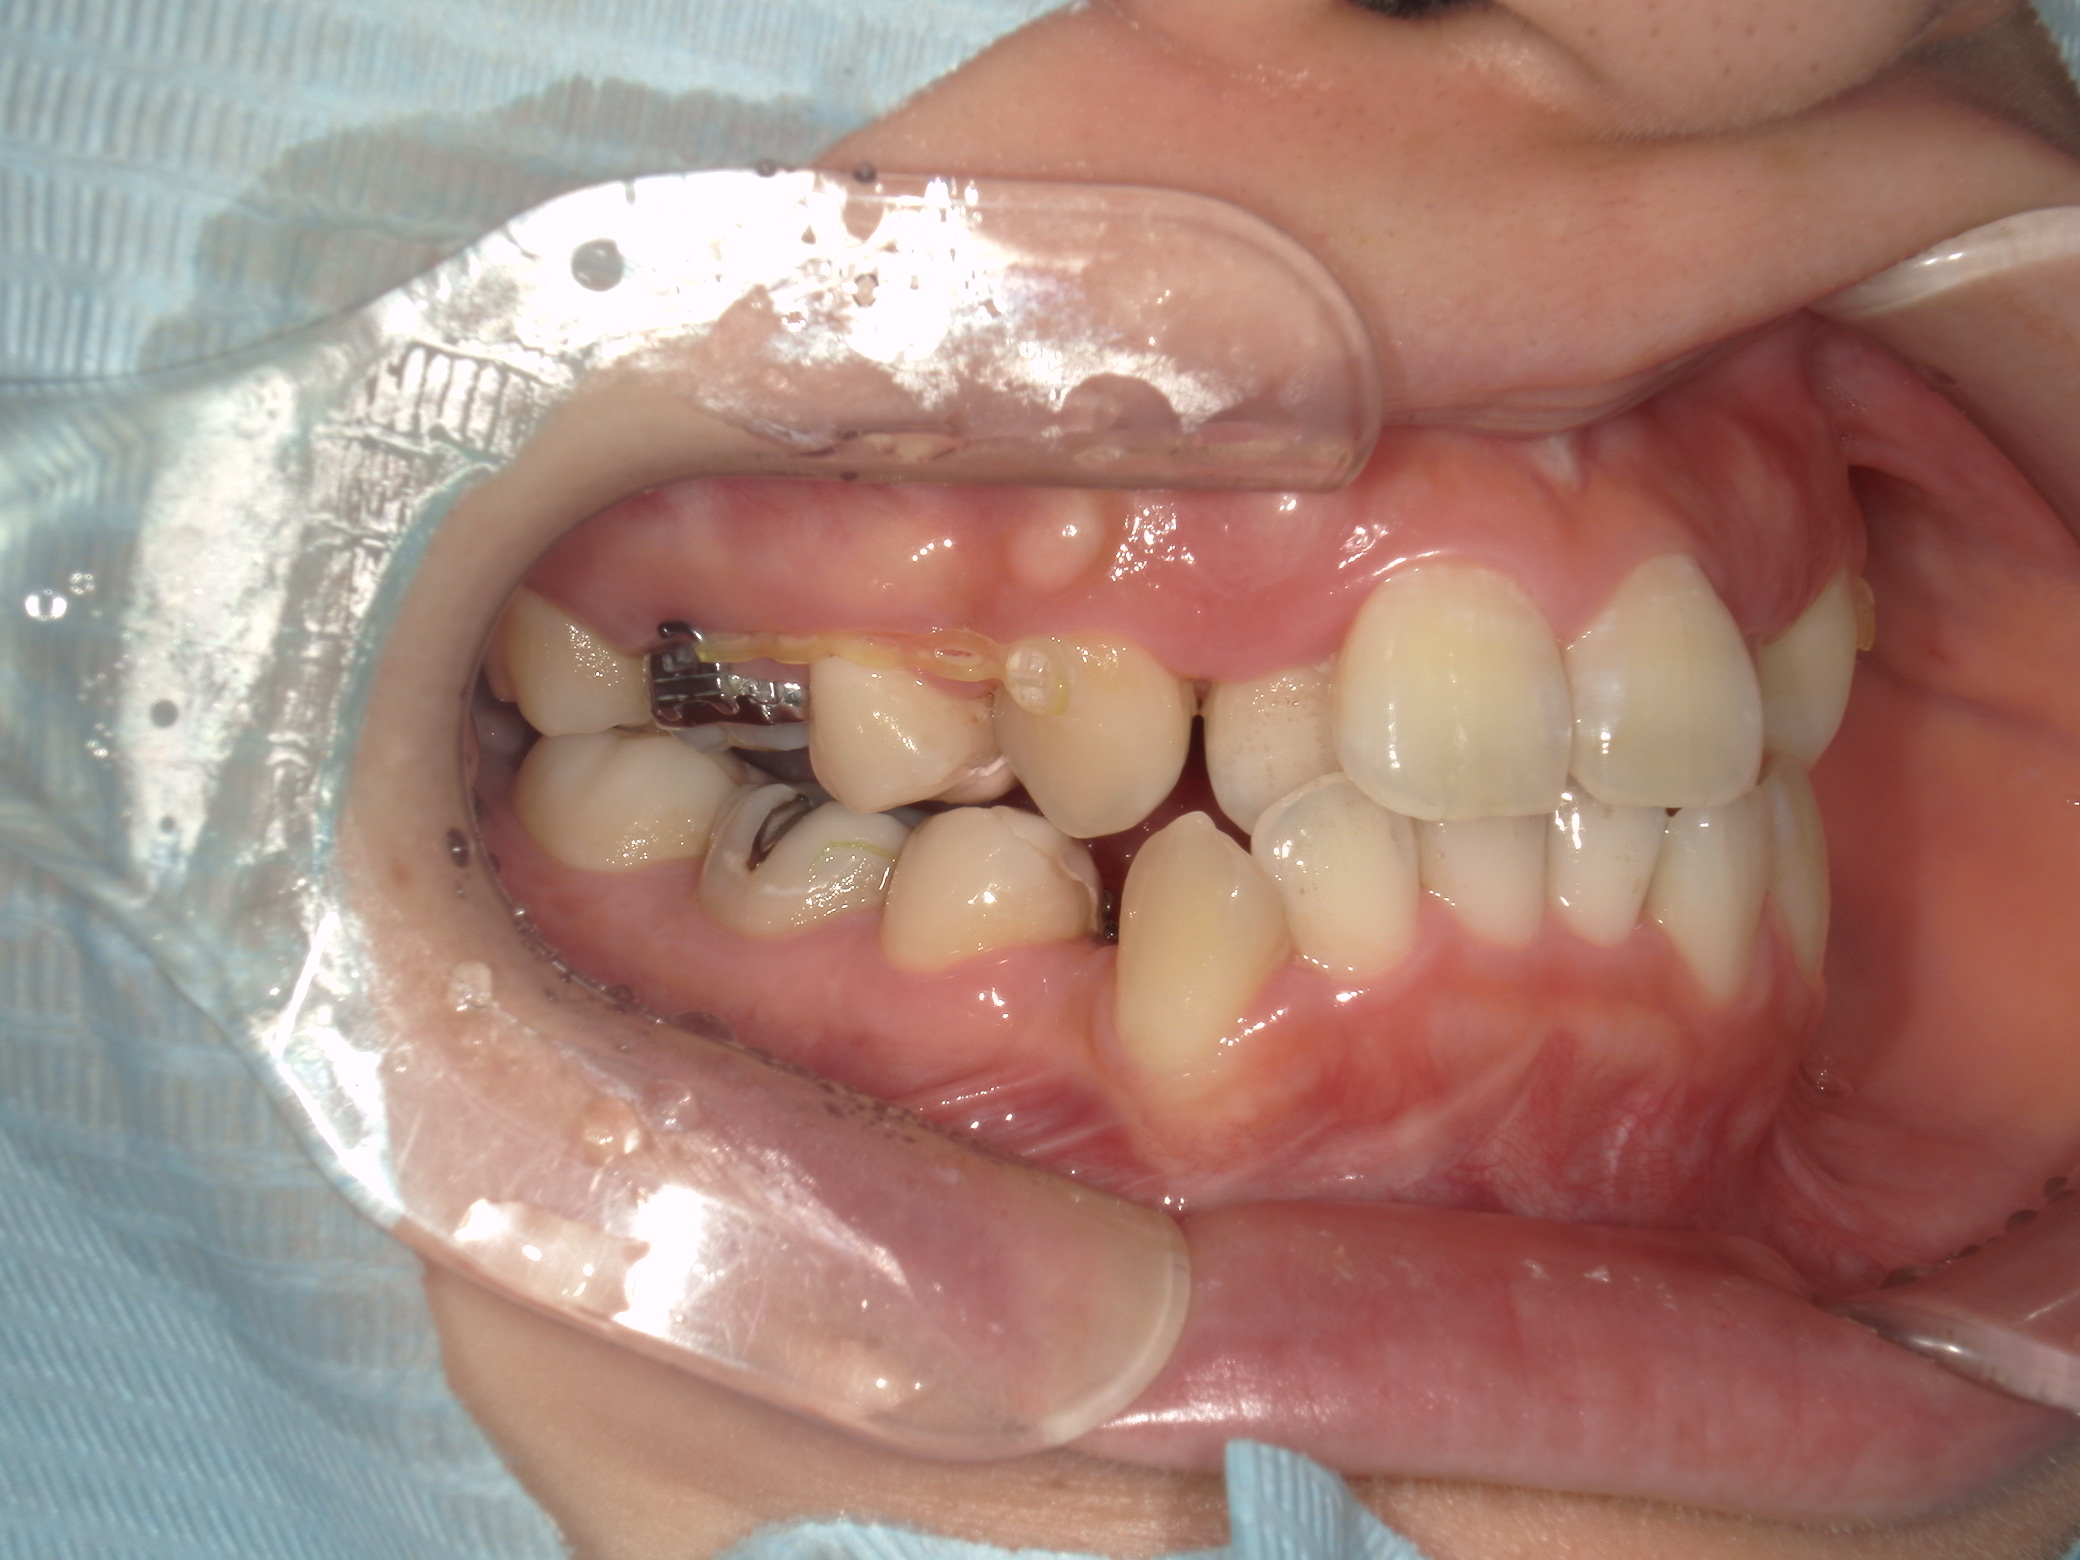

本症例は上下小臼歯抜歯により叢生解消のスペースを獲得し、下顎位の後退があることからダイレクトスプリント治療を併用して顎位の安定を求めた。

矯正用アンカースクリューは固定源の強化のために必要とした。